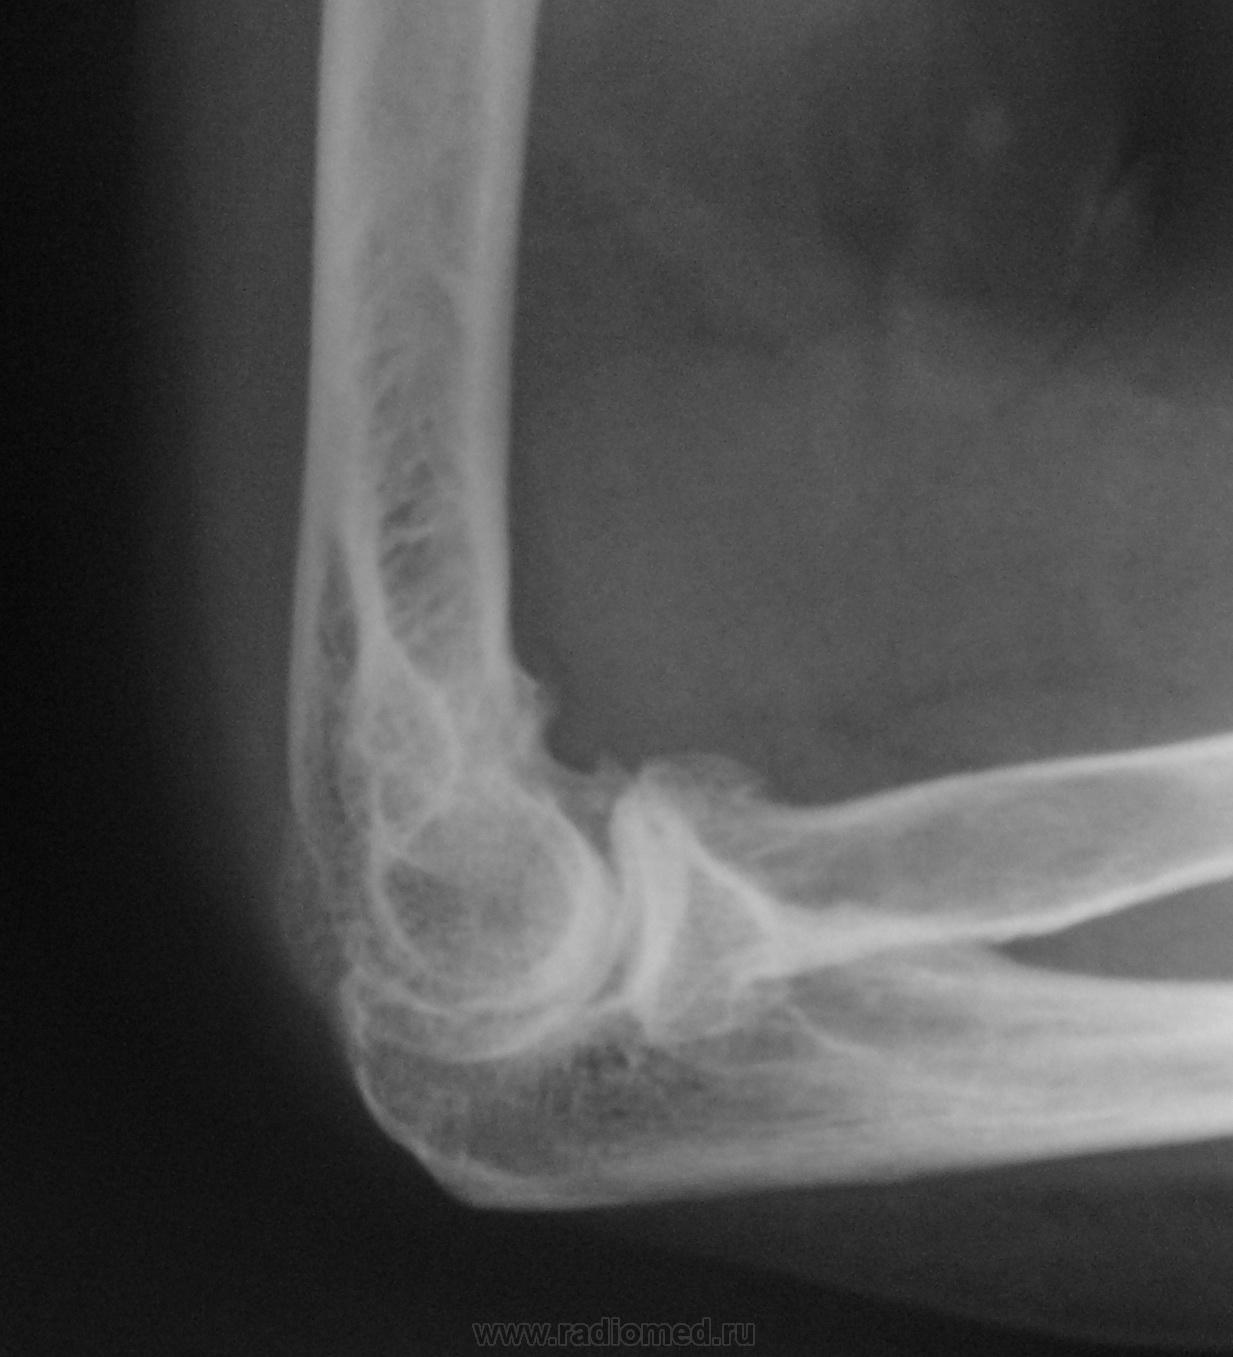

Женщина средних лет пришла на снимок локтевого сустава. Рука в суставе почти не разгибается. Сказала, что около года назад упала на локоть, попала в травмпункт. Там пообследовали и отпустили. После этого боли немного успокоились, но наступила ограниченность  движений в суставе. На мой взгляд был изолированный перелом головки луча.

На мой взгляд перелом был.

подголовчатый перелом луча был?

Согласен , что был перелом головки лучевой кости